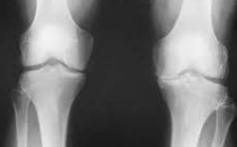

무릎 관절염으로 고생하는 환자들에게 줄기세포 치료는 인공관절 수술을 피할 수 있는 혁신적인 대안으로 주목받고 있습니다. 하지만 치료를 고려할 때 가장 먼저 궁금한 것은 바로 비용입니다. 무릎 줄기세포치료비용은 치료 방법과 병원에 따라 큰 차이를 보이며, 올바른 정보 없이는 과도한 비용을 지불할 위험이 있습니다.